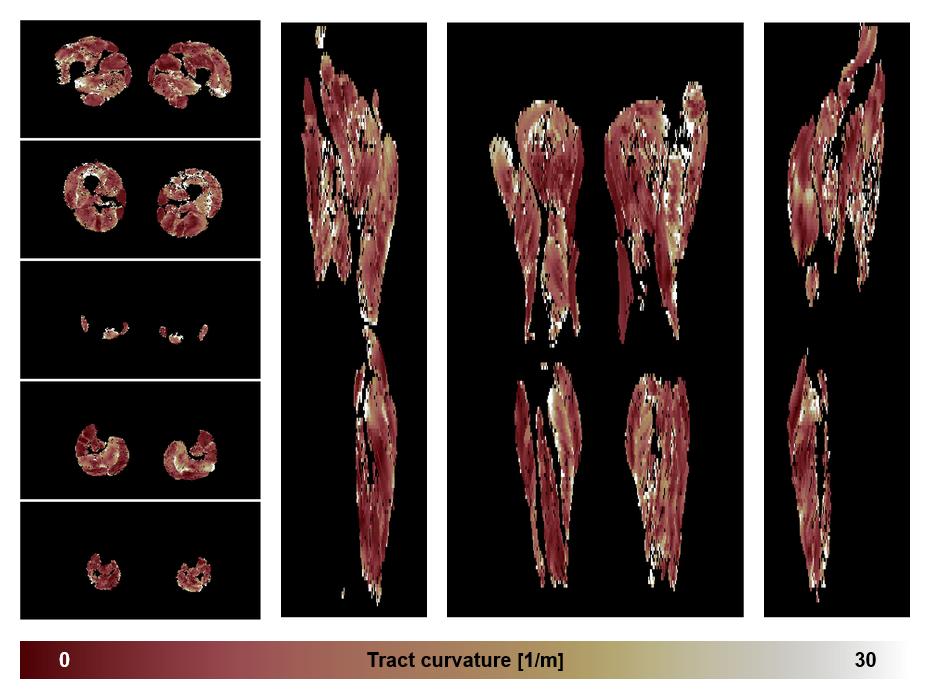

• Muscle fiber curvature map

Muscle fiber tract curvature map based on whole leg DTI based fiber tractography.